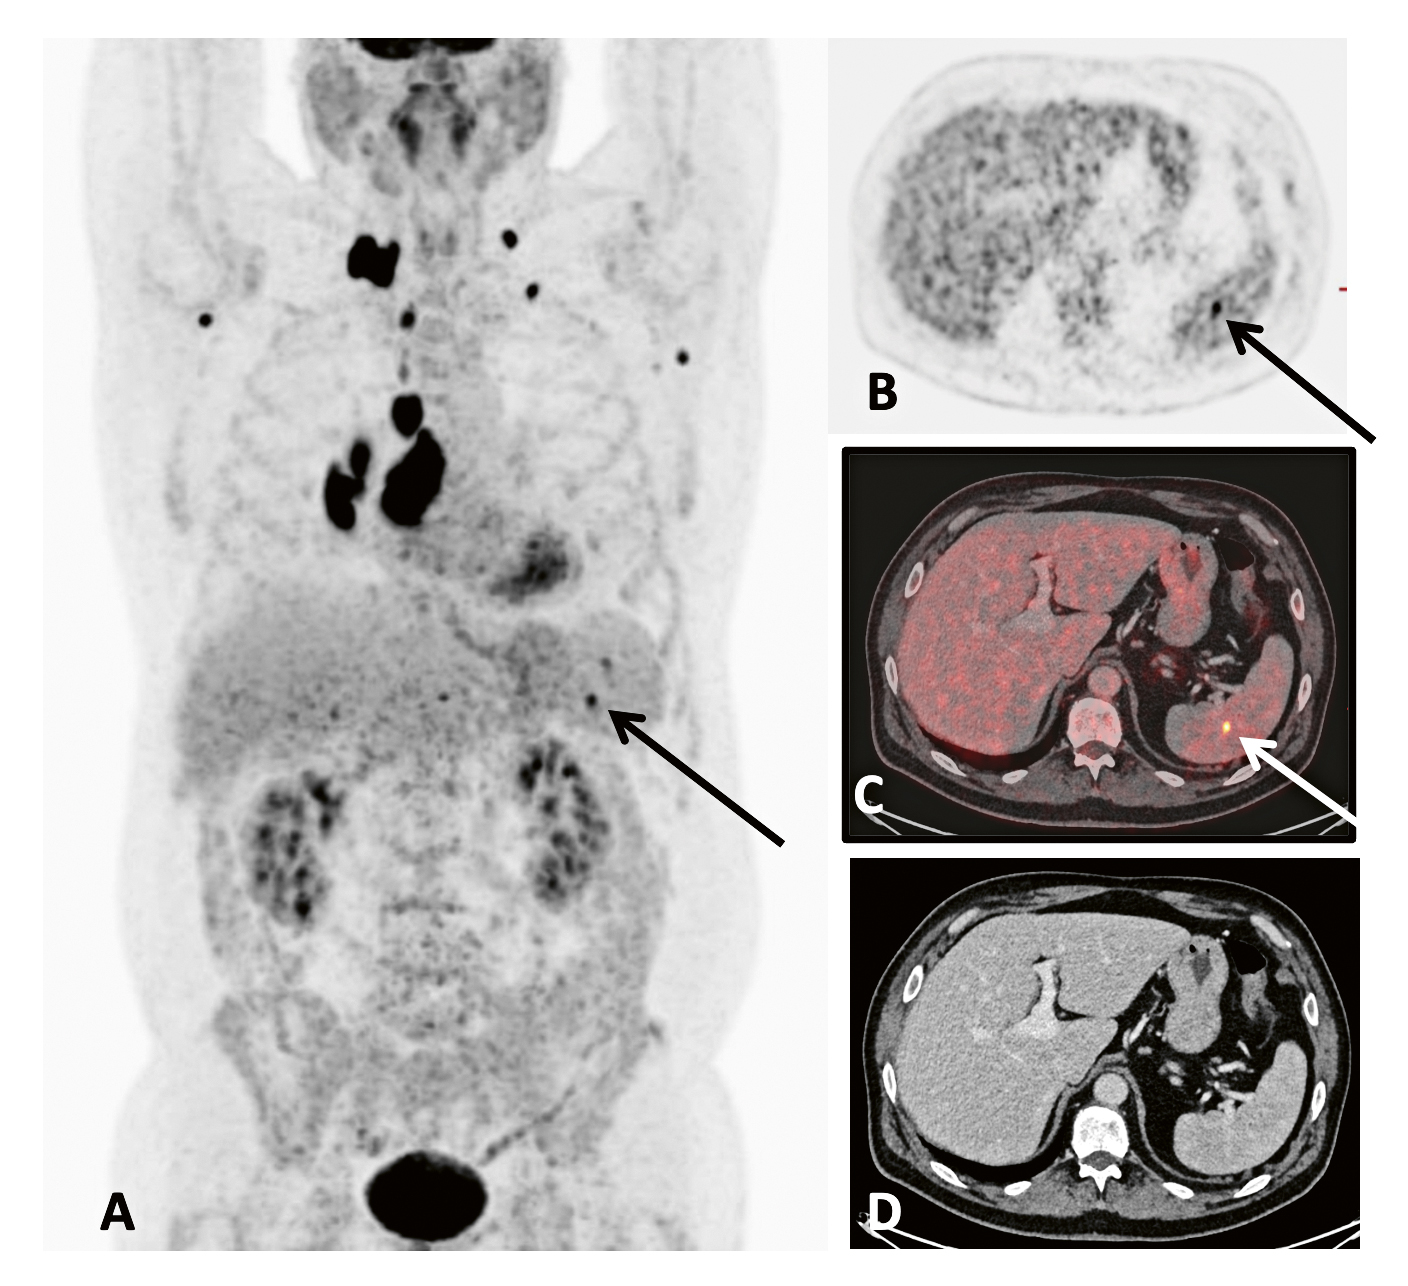

Figur 2. PET/DT-undersökning med 18F-fluorodeoxi­glukos av en patient med malignt lymfom. A. PET-registreringen visar kraftigt spårämnes­upptag i multipla tumörhärdar i torax och ett litet, distinkt tumörupptag i mjälten (pil). B–D utgör tvärsnitt i samma nivå genom mjältupptaget. Upptaget är tydligt (pil) vid PET-registreringen (B) och vid den kombinerade PET/DT-registreringen (C). Snittet från DT-registreringen (D) visar inget anatomiskt avvikande. PET-undersökningen har kunnat påvisa tumörengagement kaudalt om diafragma, vilket påverkar stadieindelningen av tumörsjukdomen. (Bild: Per Grybäck, Karolinska Universitetssjukhuset)

Positronemissionstomografi (PET), det vill säga användning av positronstrålande radionuklider, representerar nästa steg i utvecklingen. PET utgör så kallad dubbelfotondiagnostik och kräver särskild registreringsutrustning, andra radionuklider och nya radiofarmaka. PET-bilden är till sin natur digital och tomografisk samt ger högre upplösning än gammakameran. För nödvändiga korrektioner av strålningens spridning och dämpning i patienten behövs även en extern strålkälla som roterar runt patienten. Strålkällan är vanligen en DT, och hybridavbildning (PET/DT) är i dag standard (Figur 2). Även kombination med MRT förekommer. PET erbjuder, i motsats till enkelfotonavbildning, möjlighet till absolutkvantitering av radioaktiviteten i en vävnadsvolym. Aktiviteten uttrycks i SUV (standardiserade upptagsvärden) och används för värdering av ett fynd liksom för behandlingsutvärdering.